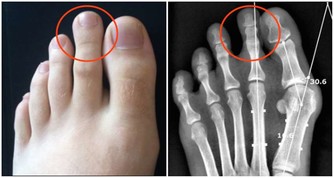

6. 我很年輕,所以我不會患癌症

雖然人們普遍認為,某些癌症的風險會隨著年齡的增長而增加,

但還有其他幾種類型的癌症,如白血病和淋巴瘤可以盯上年輕患者。

所以,建議大家始終關注身體上任何不同尋常的變化,並且及時就醫。